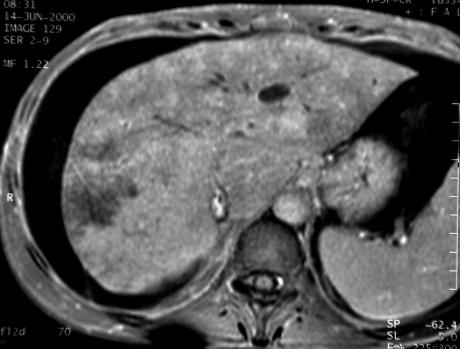

Au temps artériel

précoce le foie est très hétérogène

avec des plages où le rehaussement est franchement retardé.

Il y a une stagnation du produit de contraste dans le système porte.

Seuls les lobes caudé et une partie du segment VII sont bien vascularisés.